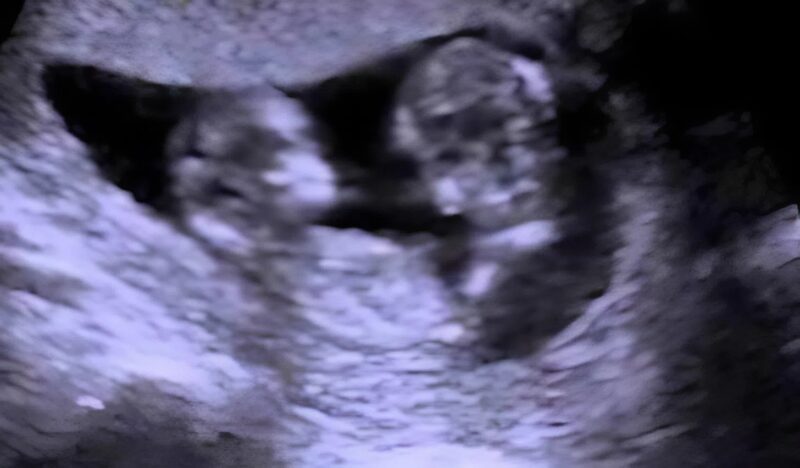

“Here are two heads… two babies… they’re lying face to face… but wait— they’re not hugging. They’re connected.”

Julia froze. Her smile disappeared as the doctor explained that the babies were conjoined at the abdomen, sharing a small part of their liver and the abdominal wall. Though they were developing normally, this tiny fusion could become a huge problem later.